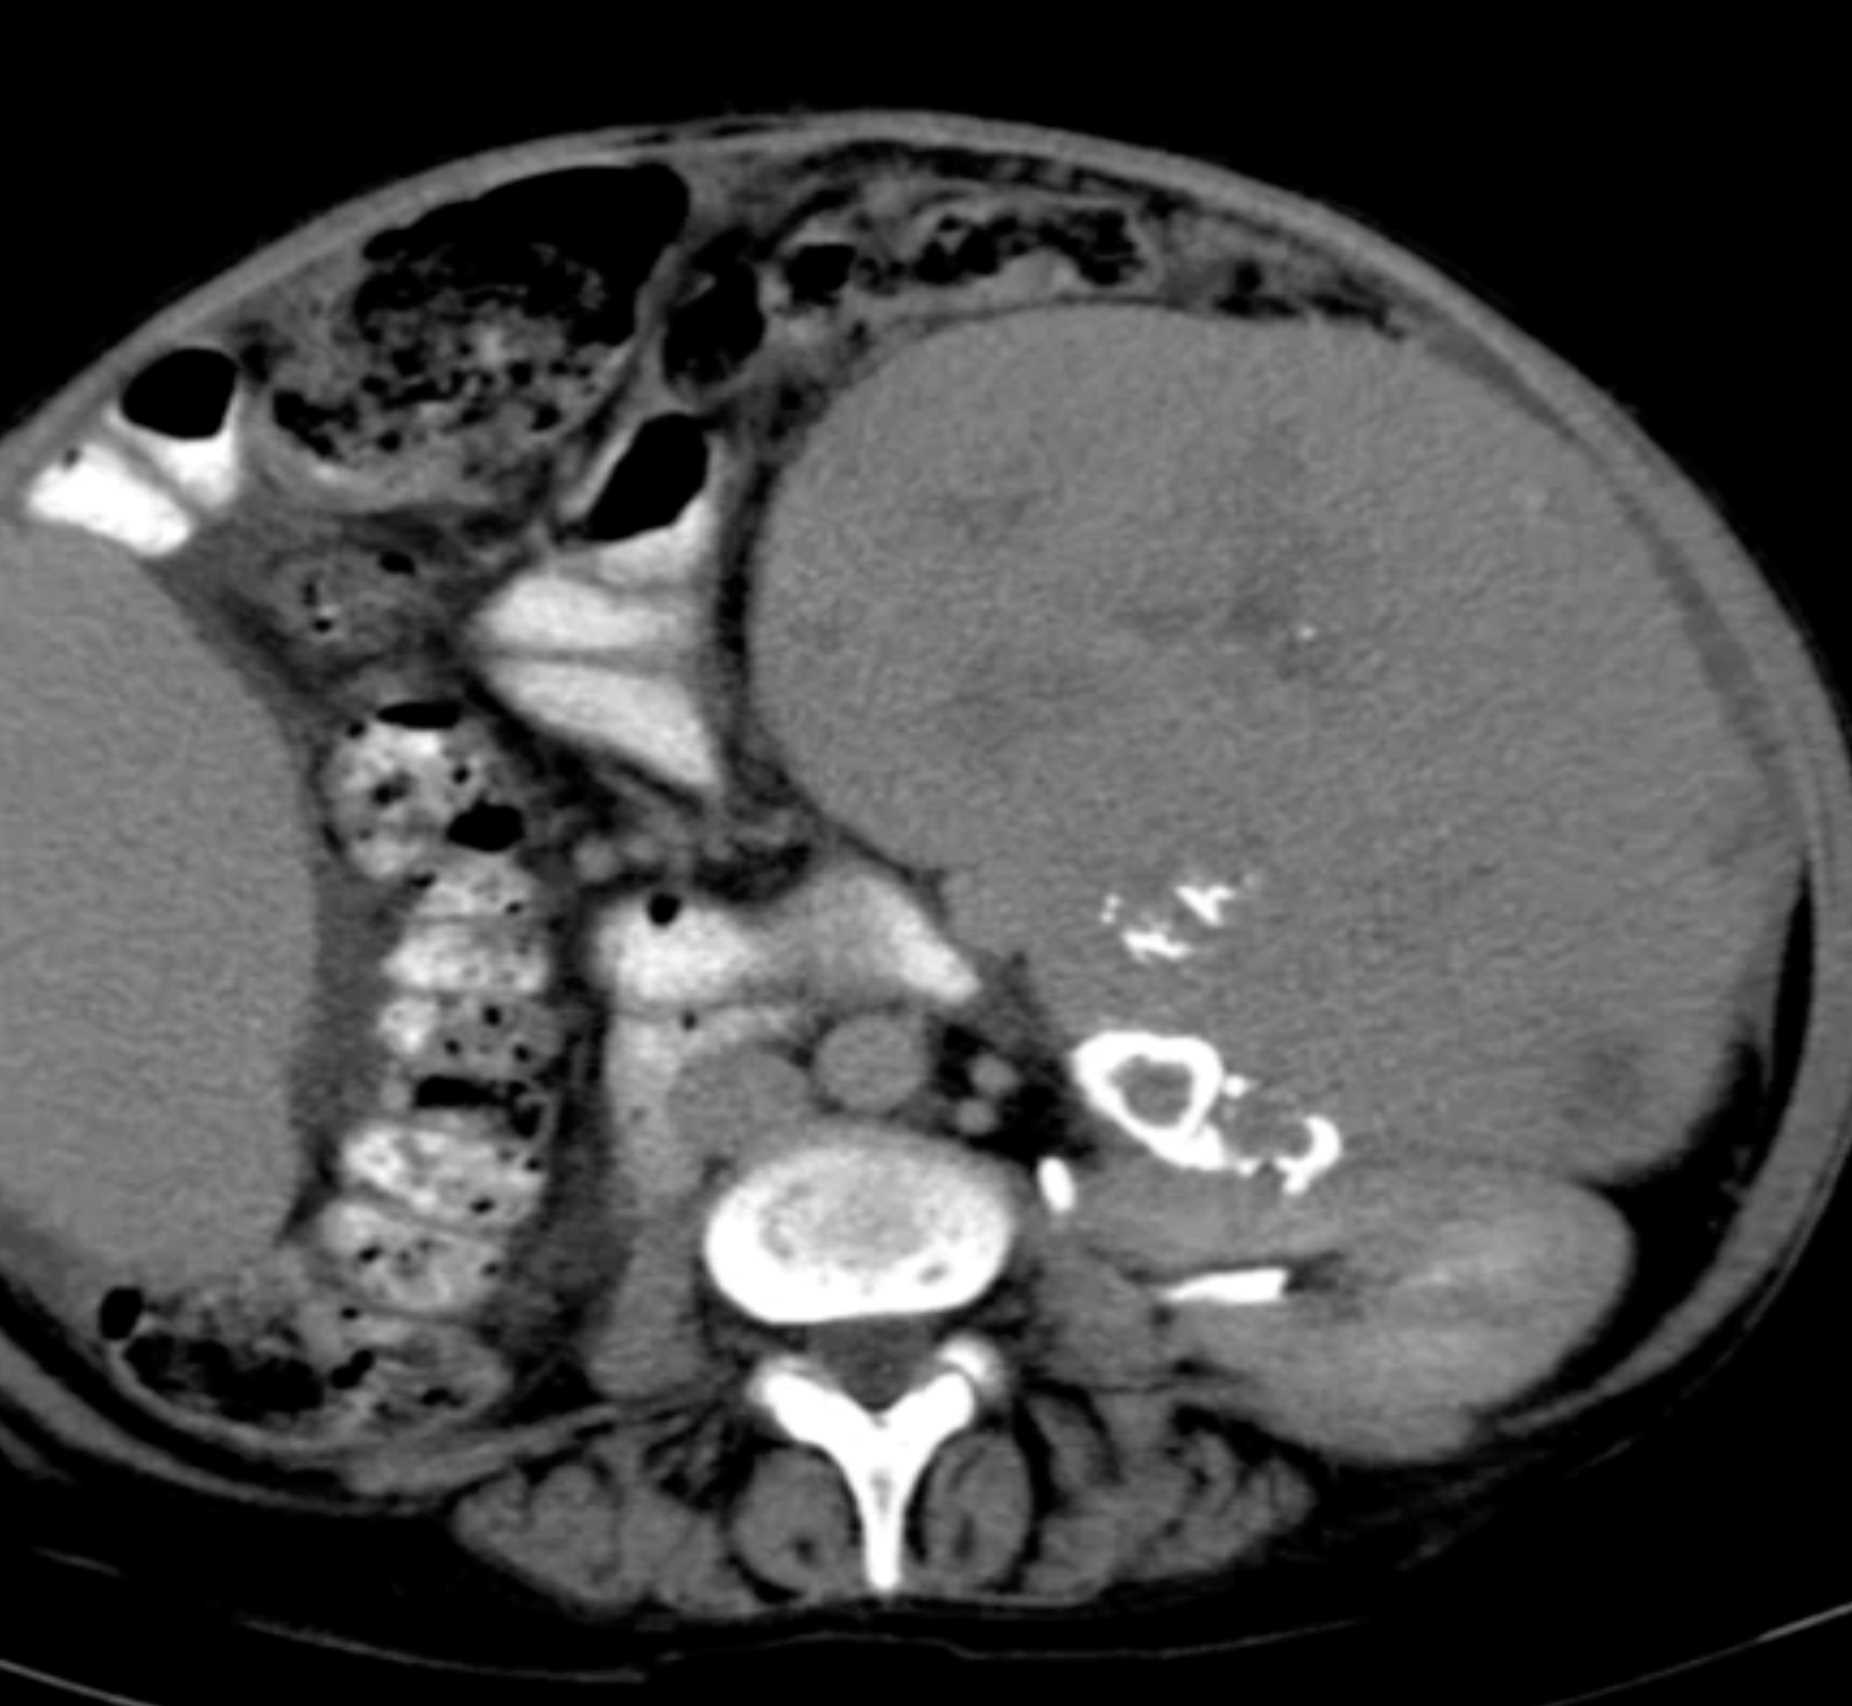

Gaucher's Spleen